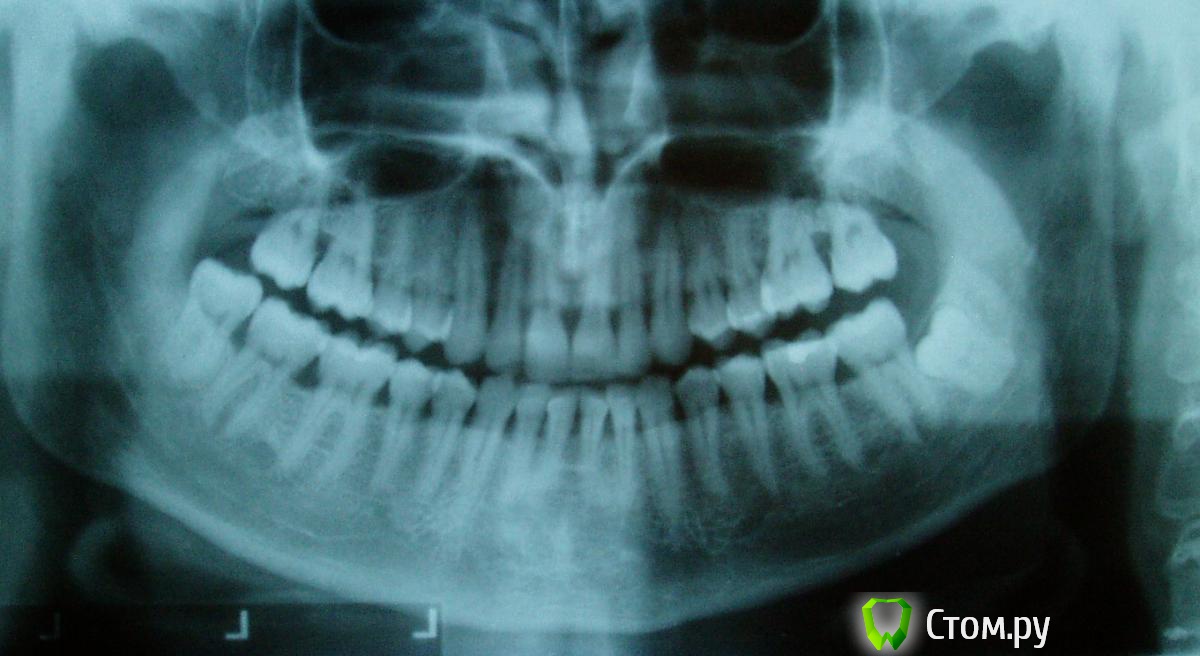

Ev127 Опубликовано 22 ноября, 2013 Поделиться Опубликовано 22 ноября, 2013 (изменено) Добрый день! Попал к стоматологам без особых жалоб, желал удалить зубной камень и замениь пломбочку. В результате направили лечиться к пародонтологу...Удаляли наддесневой камень, на следующем посещении - поддесневой с помощью закрытого кюретажа. По процедуре удаления предложили на выбор - кюретами или аппаратом Vector. Начитавшись статей в интернете я так понимаю что использование вектора делает процедуру менее болезненной и более гибкой в сложнодоступных местах, но с более-менее плотнымиотложениями лучше справляются имеено механический метод кюретами, при этом ни тот ни другой метод при глубоких карманах 100% результата не дает и в скором времени можно ждать рецидив. вобщем тут я запутался. С одной стороны я не знаю насколько глубокие карманы, поможет ли тут закрытый кюретаж(с другой сороны это врачу должно быть виднее). с другой стороны не уверен какой способ эффективнее, хотя я больше склоняюсь к механическому по финансовым соображениям: вектор 200 у.е. потив кюрет за 25у.е.... Хуже всего, реального состояния я не знаю, врач не сказала однозначно и назначила панорамный снимок. Сам я в нем ни бум-бум, может кто-то подскажет хотя-бы общее состояние. если по этому снимку можно что-то сказать(снимок не очень высокого качества..) Ну и по выбору процедуры закрытого кюретажа. Вот снимок: Изменено 22 ноября, 2013 пользователем Ev127 Ссылка на комментарий

Ev127 Опубликовано 30 октября, 2014 Автор Поделиться Опубликовано 30 октября, 2014 Господа специалисты! Посмотрите пожалуйста динамику за год. Что скажете? Где-то стало хуже? Ссылка на комментарий